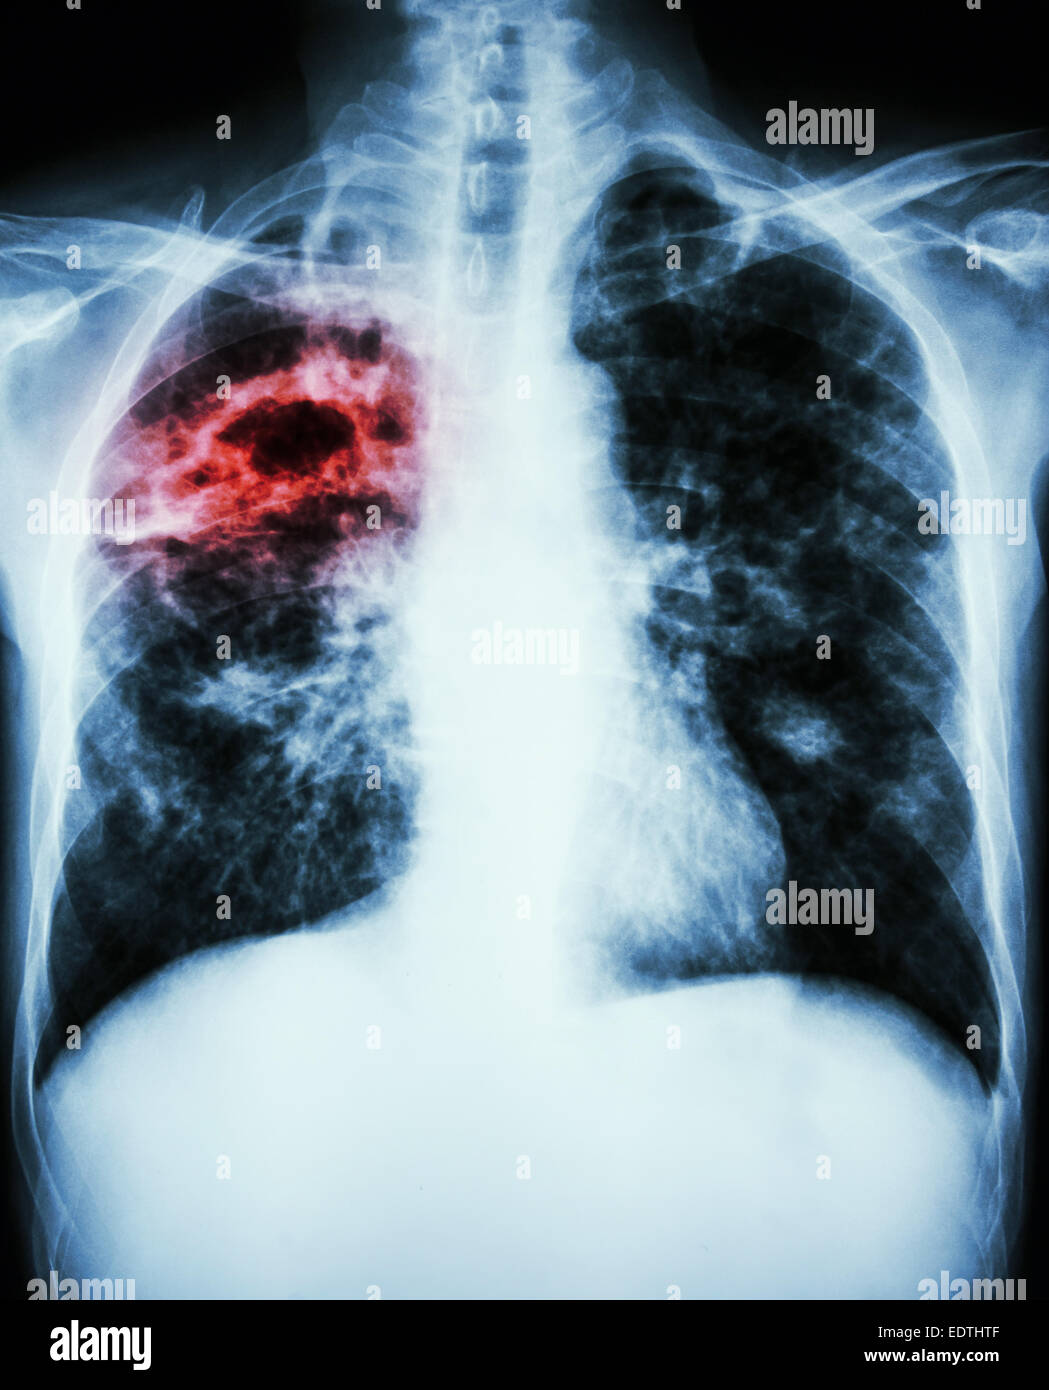

From www.alamy.com

Film chest xray show interstitial infiltration both lung Stock Photo Can An X Ray Show Lung Damage Air collecting in the space around a lung, which could cause it to collapse. Fluid in the space between your lungs and your chest wall (pleural effusion) Fluid in the lungs that might be the result of congestive heart failure. Enlarged heart which can mean you have a congenital heart defect or cardiomyopathy. The growth might be cancer, but it. Can An X Ray Show Lung Damage.